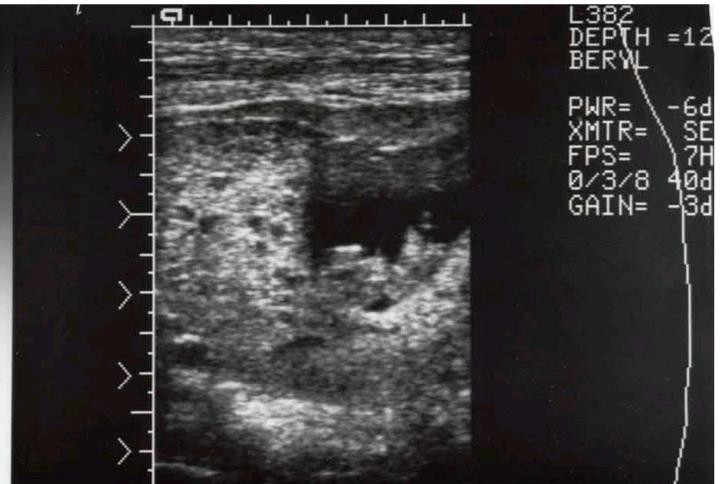

CHM USS FINDINGS- Snowstorm appearance

CHM USS FINDINGS- THECA LUTEIN CYST